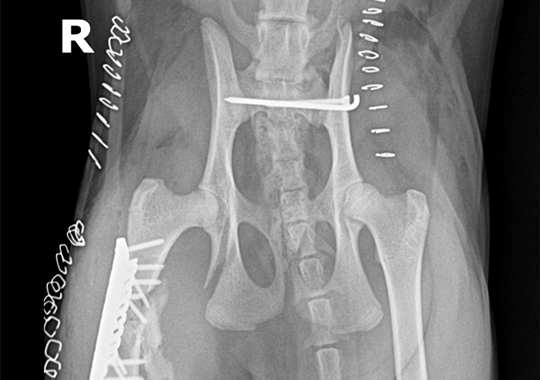

양측 슬개골 탈구

양측 4등급 슬개골 탈구 교정 (DFO) 및 좌측 십자인대 교정

대퇴골 복합골절 및 천장골분리골절 전

대퇴골 복합골절 및 천장골분리골절 후